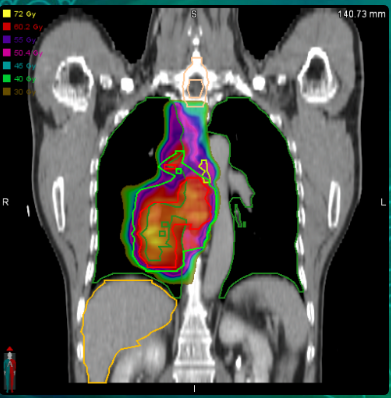

Case : Locally advanced non-small cell lung cancer

Dose Prescription:

95% PGTV 60.2 Gy/2.15 Gy/28 F

95% PTV 50.4 Gy/1.8 Gy/28 F

Protocol : RTOG0617

Techniques : IMRT/VMAT/HT